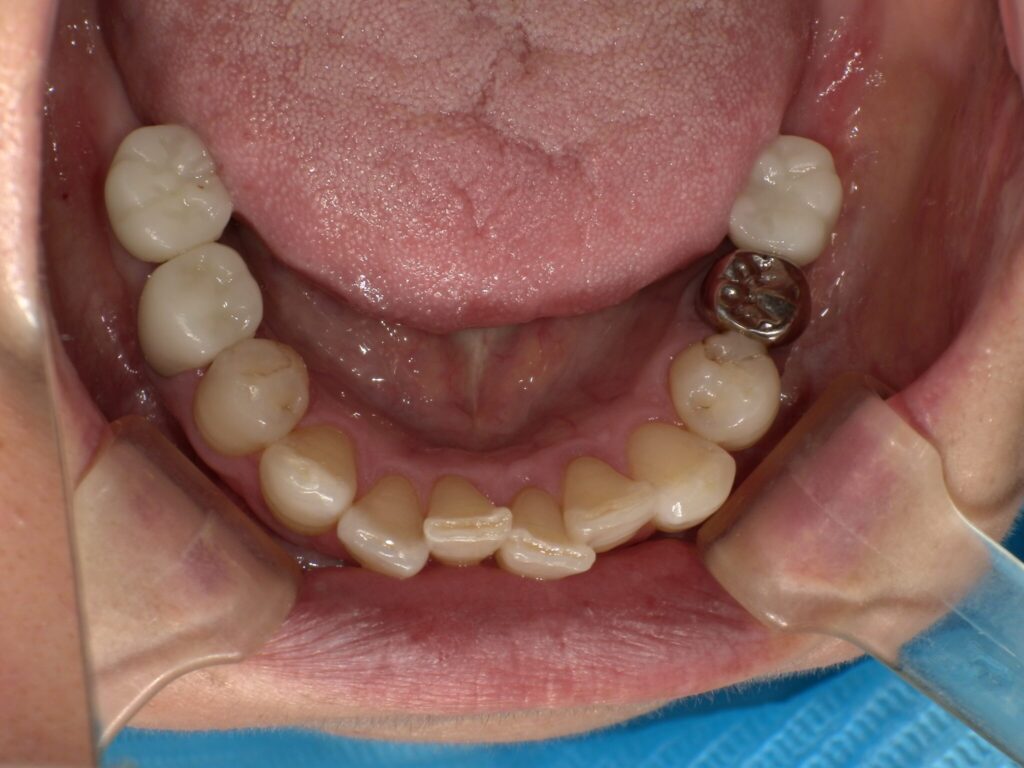

| 治療内容 | インプラント埋入(右上4・6,左上4・6,右下6,左下6) ジルコニアBr(右上3―左上3) ジルコニア(右下5,左下5) |

インプラント 1年5ヶ月/13回 ジルコニアBr、ジルコニアクラウン 3ヶ月/10回 |

| 費用 | インプラント: 2,552,000円 その他治療: 640,000円 合計 3,192,000円 *いずれも税込 |

- リスク・副作用

- 定期的なメインテナンスを行わない場合、インプラントが脱落する可能性があります。被せ物は経年的な劣化で欠ける可能性があります。